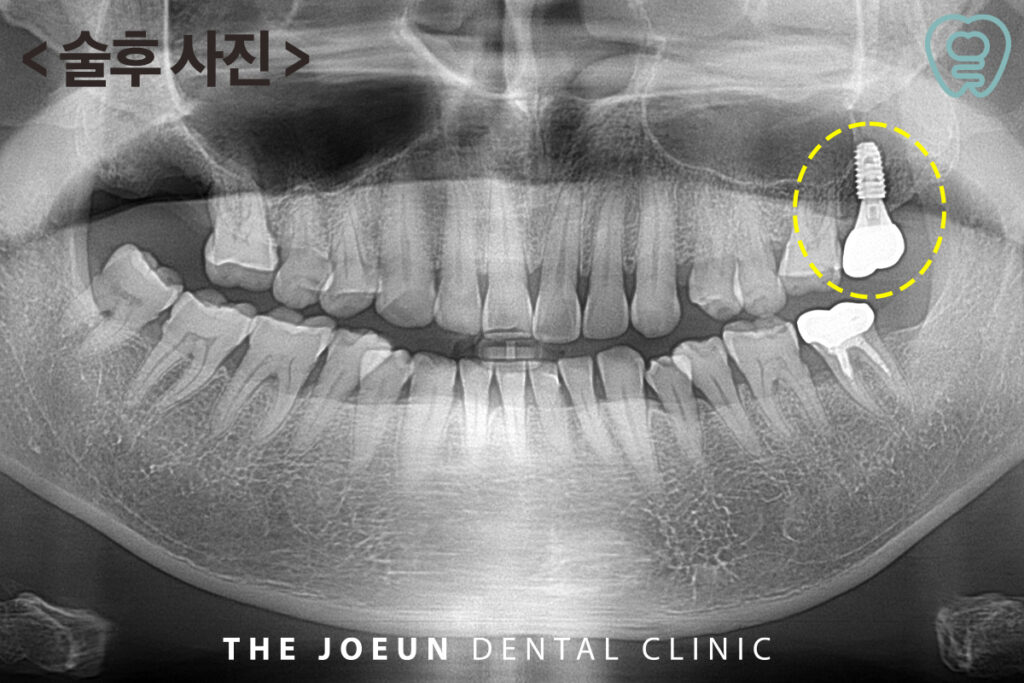

발치와 식립 후 약 3개월 만에 최종 보철물까지 마무리를 하였습니다.